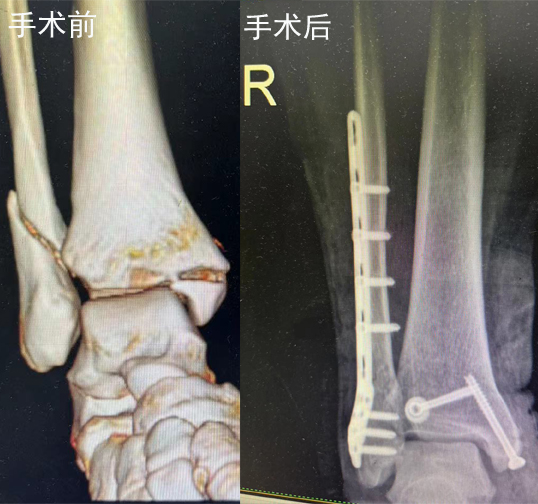

黄延峰手术治疗案例